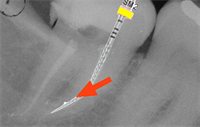

Dentaltown Learning Online- Endodontics in Depth: Modern Controlled Memory Navigation of Highly Curved Canals by Dr.Chaniotis Antonis DDS,MDSc

Dentaltown Learning Online is proud to present - Endodontics in Depth: Modern Controlled Memory Navigation of Highly Curved Canals by Dr.Chaniotis Antonis DDS,MDS. This 2 credit CE course can be found here.. Discussion of this course can be found here.... The internal anatomy of human...  Read More